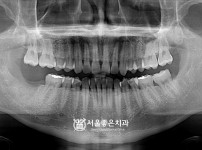

PRF 뼈이식 임플란트 1개 - 오스템 임플란트 / 오래전에 하셨던 보철 파절, 발치 후 임플란트

해당 게시물은 의료법 제56조에 의거하여 로그인 후 열람이 가능합니다.

구분 임플란트